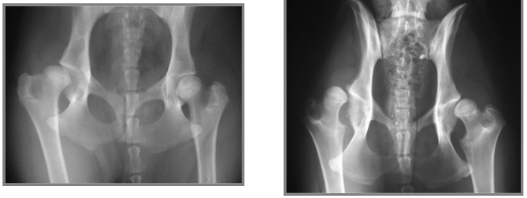

What can be seen here?

Hip dysplasia

Left: subluxated Right: completely luxated

Both can see femoral neck and acetabular changes